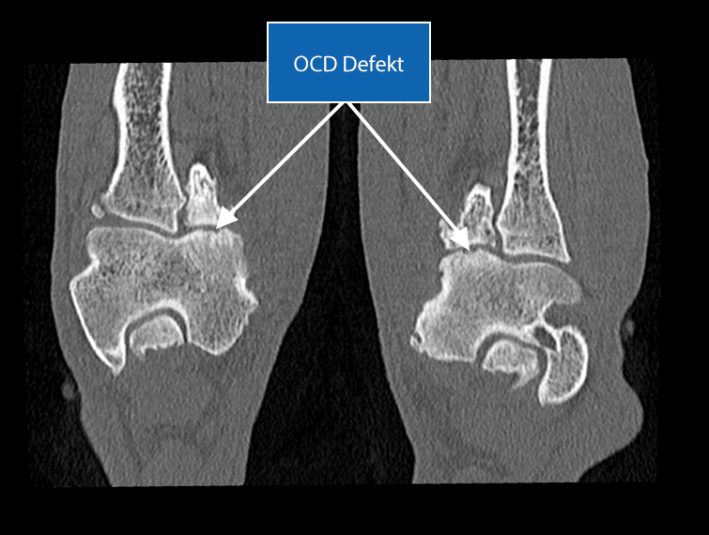

SLT Horizontalschnitt Ellbogen OCD Defektion An Beiden Medialen Condylen Des Humeru Deutliche Sklerose Am Medialen Condylus Humeri

Durch eine Verknöcherungsstörung des inneren Gelenkknorpels am Humerus condylus können Knochenkrater enstehen, welche im CT erkennbar sind (OCD Defekt).